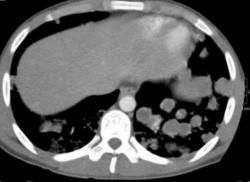

Метастазы. Наблюдение Владимира Борисовича Серова.

Метастазы. Наблюдение Владимира Борисовича Серова.

Множественные метастазы.